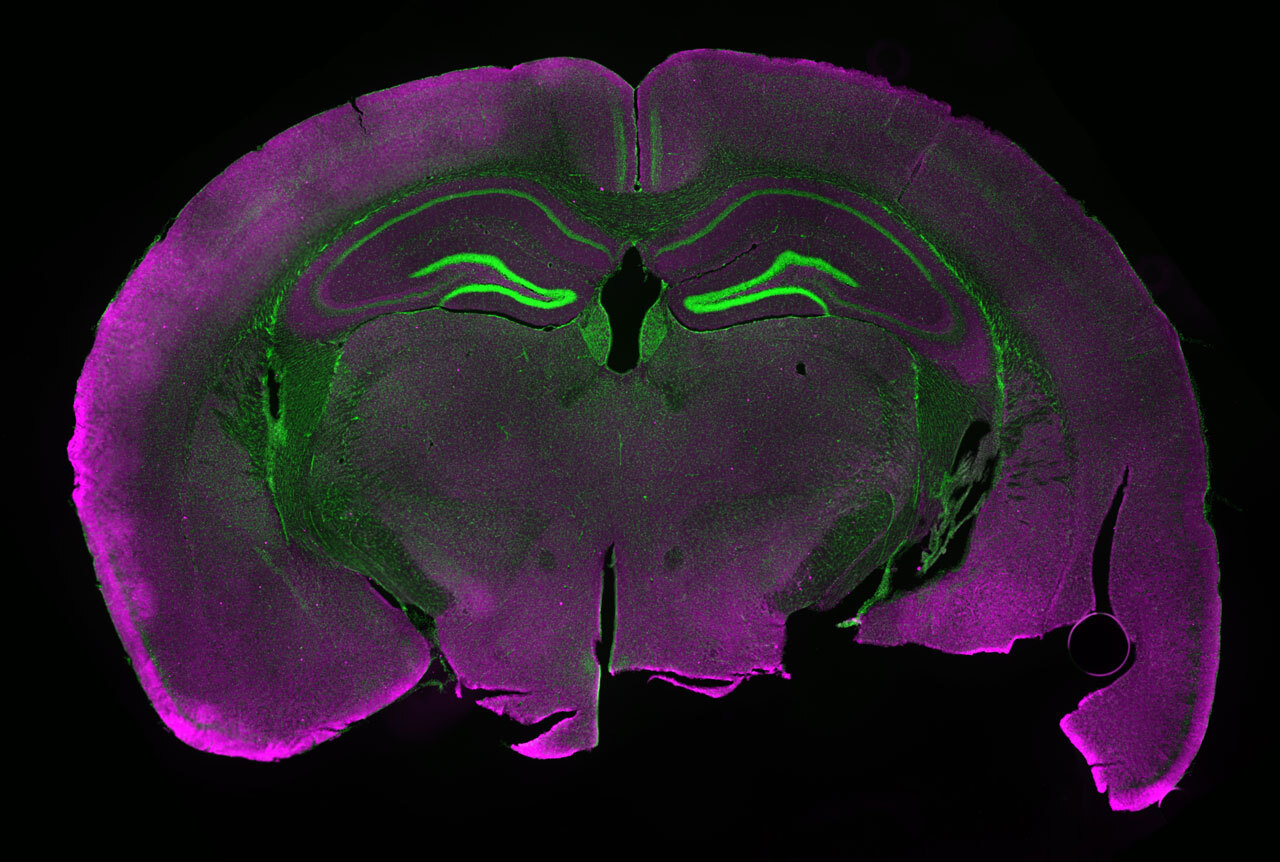

На специально выведенных мышах с возможностью визуализации нейронной активности и управления ею Мартен и его коллеги смогли идентифицировать небольшую группу нервных клеток, реагирующих на чрезмерное употребление алкоголя.

Когда нейроны активируются у подопытных животных, вырабатывается флуоресцентный белок, который можно увидеть с помощью волоконной фотометрии. Поскольку это происходит в реальном времени, ученые могут точно определить, какие нейроны активируются при воздействии стимула. Затем, используя оптогенетику (метод безопасной активации клеток светом у живых организмов), эти нейроны можно включать и выключать, словно тумблер. Это позволяет наблюдать изменения в поведении и связывать их с конкретными нейронами.